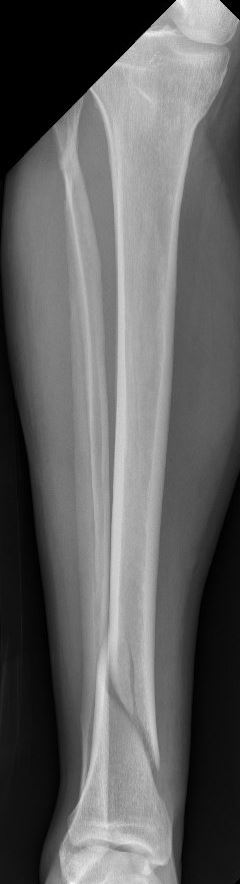

Het onderbeen bestaat uit twee lange botten; het scheenbeen en het kuitbeen. Het scheenbeen vormt samen met het bovenbeen het kniegewricht en het scheenbeen en het kuitbeen samen vormen met de voet het enkelgewricht. Het scheenbeen is vele malen dikker en sterker dan het kuitbeen en draagt veruit het meeste gewicht van het lichaam.

Omdat het scheenbeen een erg sterk bot is, is er vaak veel energie nodig om het onderbeen te breken. Vaak gaat het om een verkeersongeval, een val van hoogte, maar ook soms een harde directe trap tegen het onderbeen. Bij een breuk van het onderbeen is er in principe sprake van een breuk van zowel het scheenbeen als het kuitbeen. Soms is alleen het scheenbeen gebroken. Indien alleen het kuitbeen gebroken is, spreken we niet van een onderbeenbreuk, maar meestal is er dan sprake van een gebroken enkel of een geïsoleerde kuitbeenbreuk. Omdat bij een onderbeenbreuk meestal beide botten gebroken zijn, is er vaak sprake van instabiliteit van het onderbeen. Behalve een letsel van het bot is er ook vaak letsel van de zogeheten weke delen, zoals huid, pezen, spieren en eventueel zelfs bloedvaten of zenuwen. Indien er sprake is van een ernstig letsel van de weke delen, kan dit leiden tot een open breuk (het bot komt dan in contact met buitenlucht) of zelfs uitval van de zenuwen en/of bloedvaten.